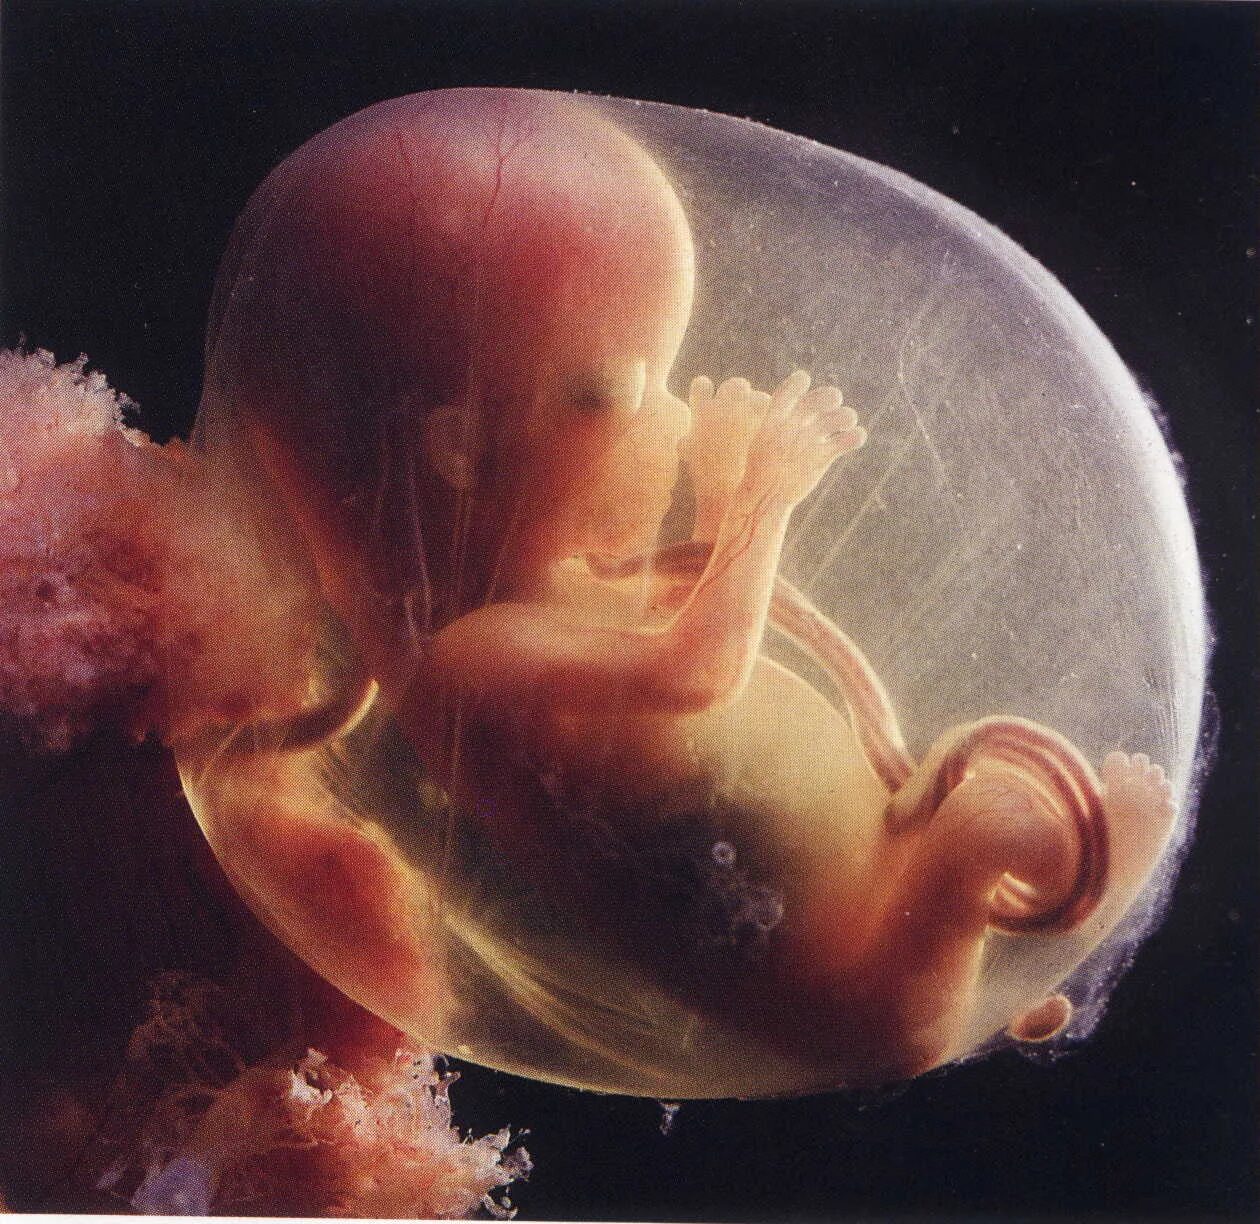

13 недель как выглядит малыш